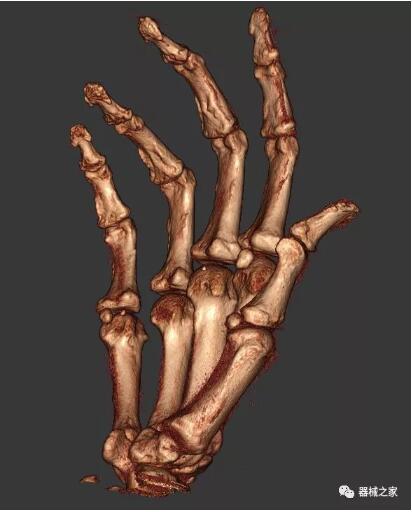

另外一款被稱為世界上最小的CT,它的重量僅300磅,不僅能夠掃查足部,還可以檢查膝蓋和上肢等。

這款CT使用非常方便,通過上下移動保持與患者的手臂或者雙腿齊平,掃描快速,僅需要30秒左右就可以完成掃查。

以上介紹的CT均來自國外同一家公司,這些CT均配置了可視化軟件,可以進行切片、3D重建以及大型CT附帶的所有典型的操作功能。

以下是這些“特立獨行”的CT所拍出來的圖像: